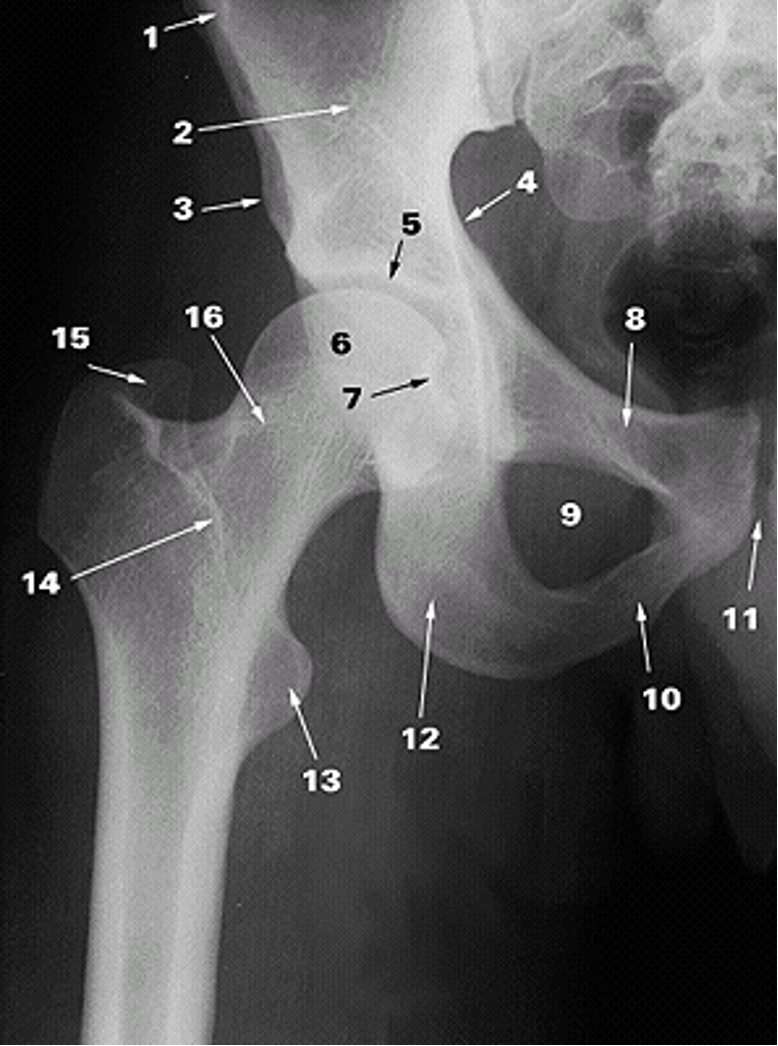

<p>1.</p>

Anterior Superior Iliac Spine (2)

<p>2.</p>

Ilium (2)

<p>3.</p>

Anterior Inferior Iliac Spine (2)

<p>4.</p>

Pelvic Brim

<p>5.</p>

Acetabular Fossa (2)

<p>6.</p>

Head of Femur (2)

<p>7.</p>

Fovea

<p>8.</p>

Superior Ramus of Pubis (2)

<p>9.</p>

Obturator Foramen (2)

<p>10.</p>

Inferior Ramus of Pubis (2)

<p>11.</p>

Pubic Symphysis (2)

<p>12.</p>

Ischium

<p>13.</p>

Lesser Trochanter (2)

<p>14.</p>

Intertrochanteric Crest (2)

<p>15.</p>

Greater Trochanter (2)

<p>16.</p>

Neck of Femur (2)